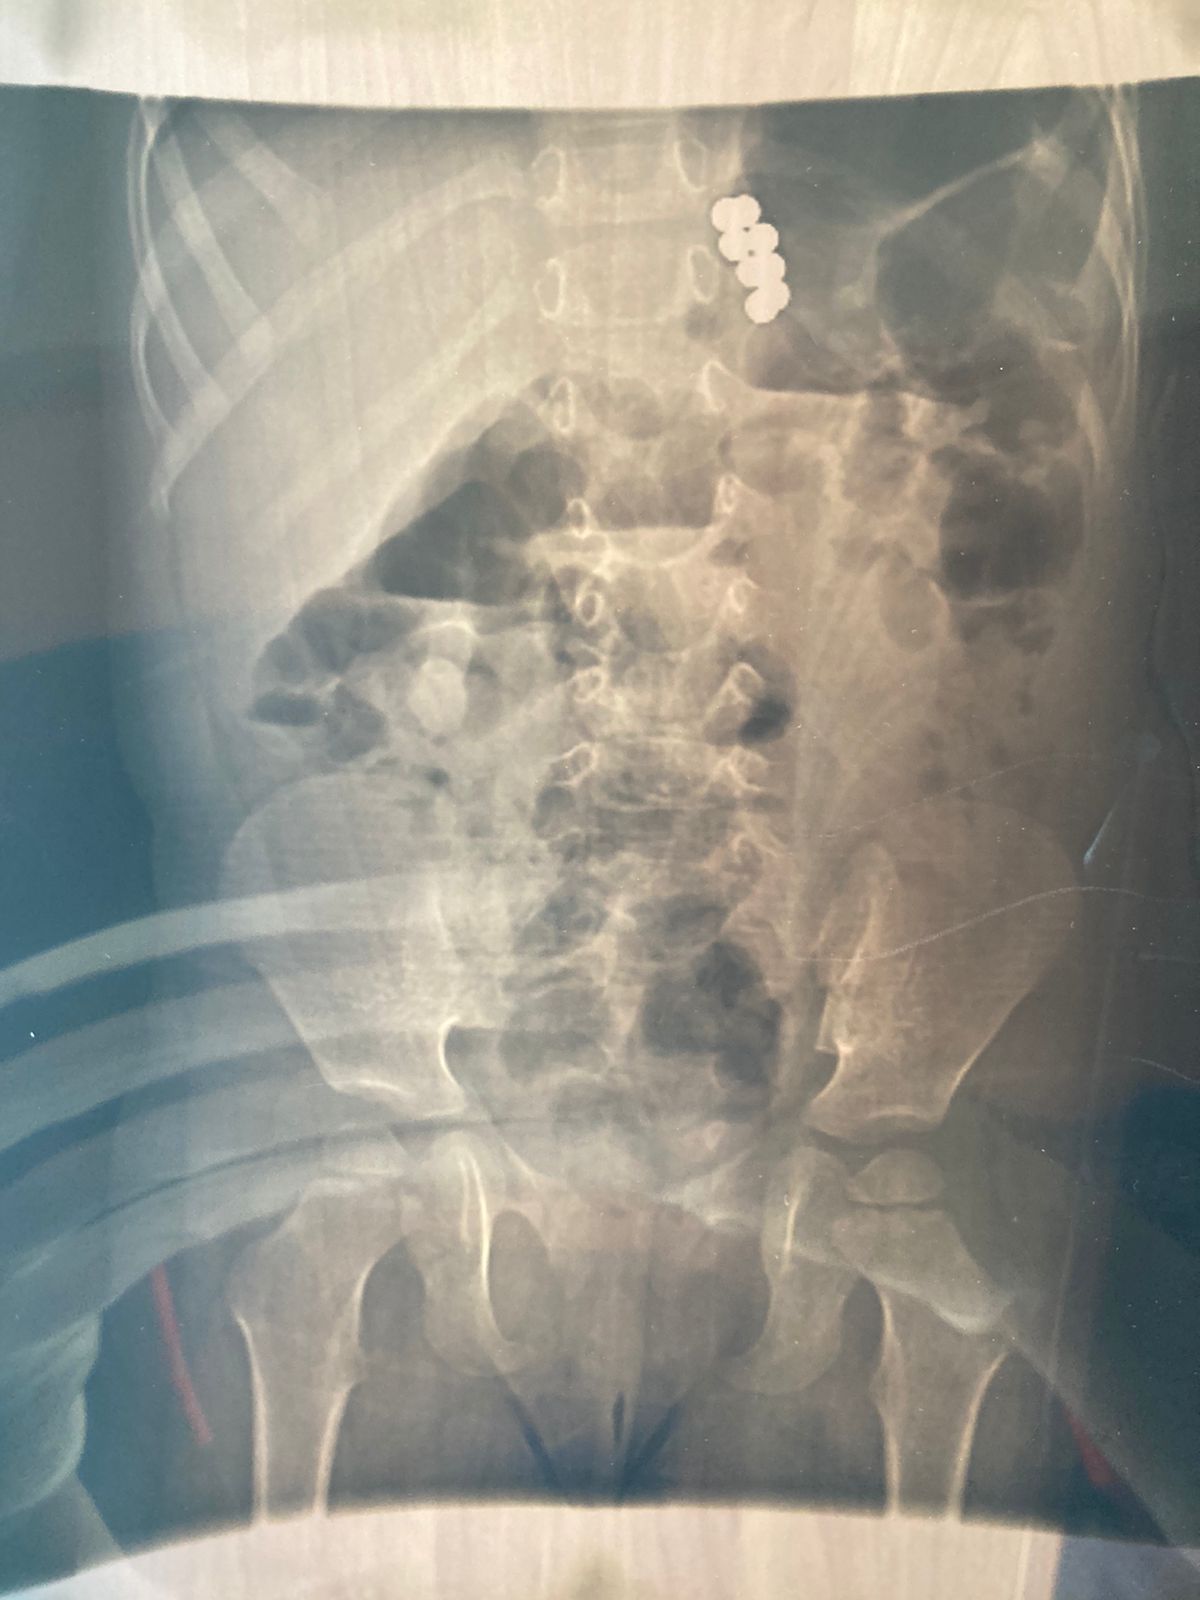

Рентген показал наличие у маленького пациента 8 магнитных шариков в пищеварительном тракте. Под общей анестезией врач провел эндоскопическое исследование и удалил их. Шарики пробыли в организме ребенка недолго, поэтому не успели нанести серьезный вред.